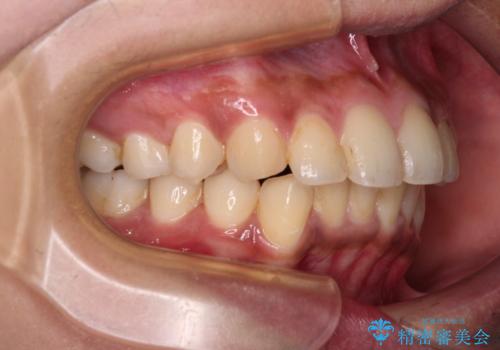

深い咬み合わせと前歯のデコボコ インビザラインによる矯正治療

- 前歯のデコボコと、食いしばりやすい咬み合わせを気にして来院された患者様です。

骨格的に下顎骨が左側に偏位しており、インビザラインでの矯正治療では奥歯の咬みにくさが残る仕上がりが懸念されましたが、新幹線での通院となるため、来院回数の少ないインビザラインでの治療を希望されました。

リスクをご説明した上で、インビザラインにより気になっている叢生と深い咬み合わせを改善していくこととしました。

治療途中では、左右ともに奥歯が咬みにくい状態が続き、問題なく噛めるようになるまでに長期間を要しました。

一方で、デコボコや下顎の前歯が隠れてしまうほどの深い咬み合わせはしっかりと改善されました。